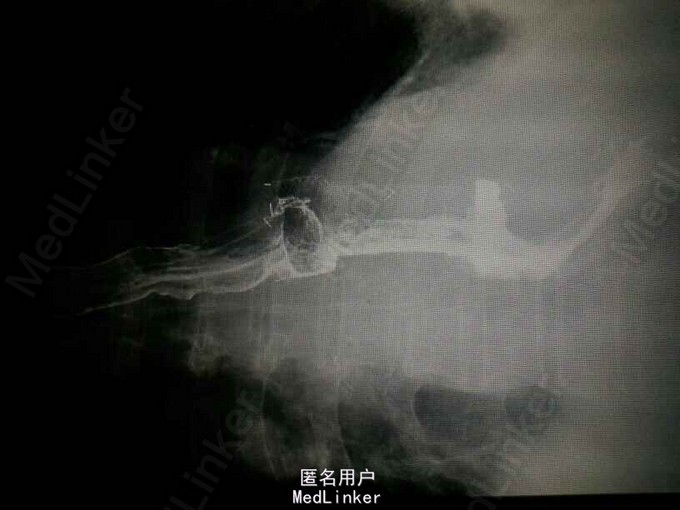

查体:气管居中,左肺呼吸音弱,右肺呼吸音尚可。未闻及湿啰音。胸腔引流管可见褐色浑浊液体引出。 腹部CT肝脾胰未见异常,胆总管扩张。 食管造影:食管下端撕裂,食管胸膜瘘。 胸CT左肺气胸,左侧胸腔内高密度影,考虑造影剂漏入胸腔。左肺实变,右侧少量胸腔积液。

诊断:自发性食管破裂。 治疗:急诊行胸腔闭式引流。后行左剖胸食管破裂修补。术中见胸腔污染严重,见菜叶,消化液等。后纵膈可见较多脓性分泌物,食物残渣,坏死组织。食管裂口处上方可见5cm纵向肌层及粘膜层撕裂口,相应位置处可见纵膈胸膜撕裂口。术后予肠内肠外营养,舒普深,泰能,稳可信,抗感染,术后反复行2次食管造影,仍存在食管破裂口,术后一月行胃镜及食管支架植入术。第二天行进食流质及半流质通畅,平稳出院。